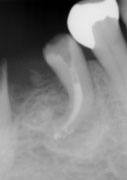

したがって、院長が大学生だった時に学んだ、ステンレススチールのファイル(根の中を掃除する道具)では根の湾曲に追従しないため、当院では全症例ニッケルチタンという柔軟な新しい素材で作られたファイル(従来のステンレススチールに比べ約5倍高価)で根の神経をとった穴を清掃しています(図3)。

図3